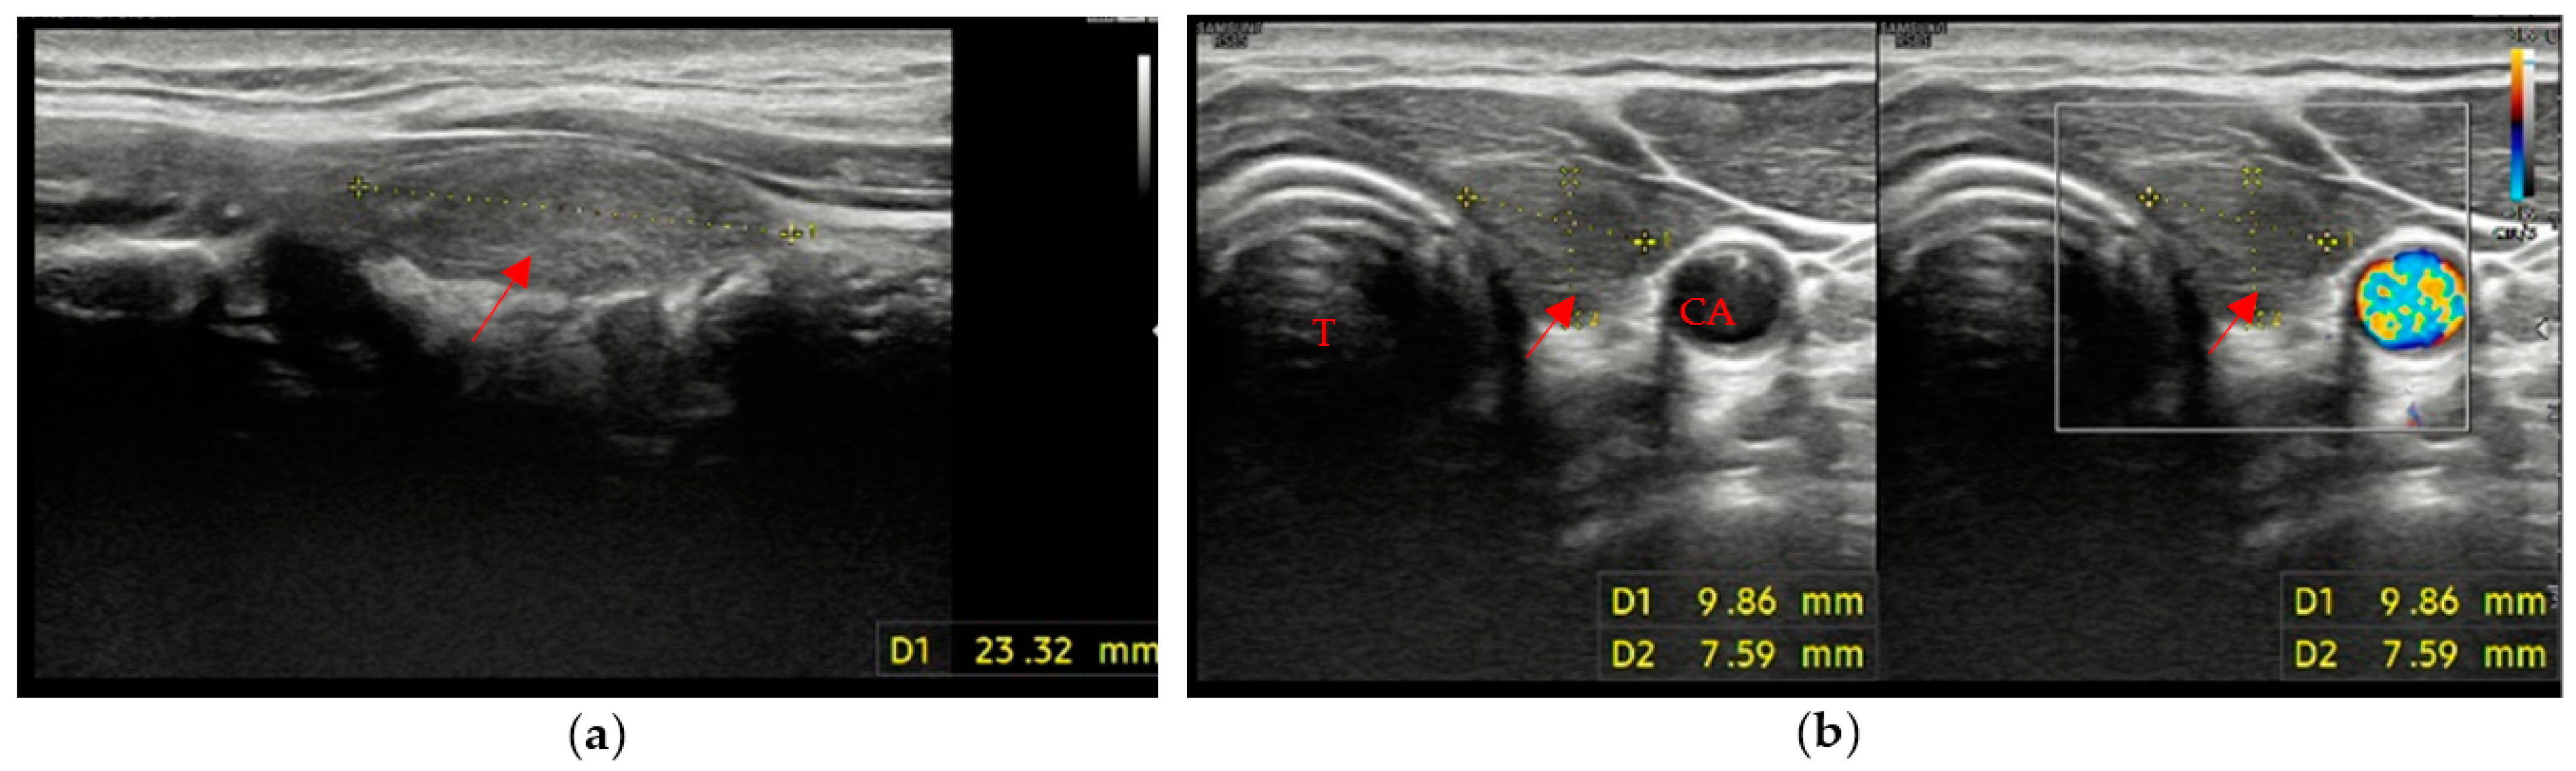

• A mildly hypoechoic or isoechoic pattern with ill-defined margins was found in 23 patients, which is approximately 58% of patients with evidence of residual swab (Figure 2a,b).

Figure 2. Residual swab pattern (red arrow) 2, characterized by a mildly hypoechoic/isoechoic ecostructure and ill-defined margins; (a) Longitudinal view; (b) Axial view. No vascular signal is seen at Color Doppler. Carotid artery (CA) and Trachea (T).